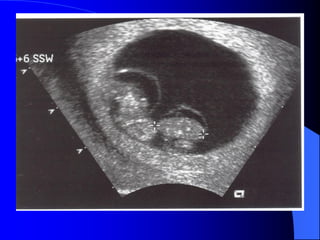

Theo quy taéc Hellin, taàn suaát sinh ñoâi laø

1/85 thai kyø, sinh ba 1/85 vaø sinh tö 1/85.